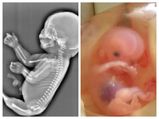

கர்ப்ப காலத்தில் தாயின் வயிற்றில் குழந்தைகளின் நிலை: ஸ்கேன் படங்கள்!